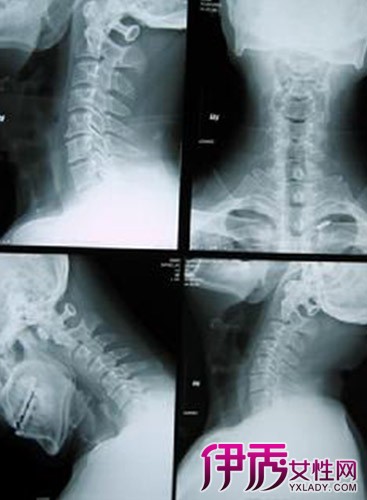

【图】颈椎病的症状有哪些 如何治疗颈椎病比较有效

颈椎病会出现哪些严重的症状?颈椎病是一种非常见的疾病,多常常表现为颈肩痛、头晕头痛等。广州文明微创医院骨科专家刘文胜院长表示,颈椎病患者早期如果不能得到及时治疗,病情会有不同程度的进展,从而导致出现一些颈椎病严重的症状。下面介绍的几种颈椎病严重症状,希望大家能引起重视,并注意预防。